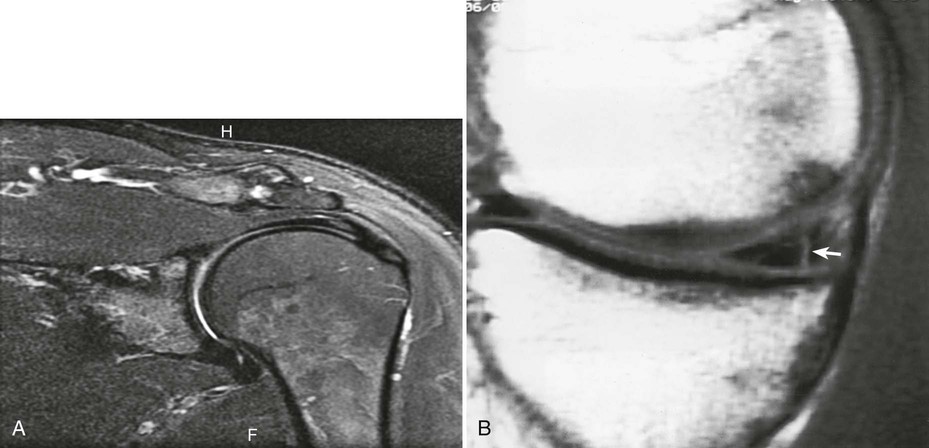

After double-contrast shoulder arthrography is performed, computed tomography (CT) may be used to examine some patients. CT images may be obtained at approximately 5-mm intervals through the shoulder joint. In shoulder arthrography, CT has been found to be sensitive and reliable in diagnosis. Radiographs and CT scans of the same patient are presented in Figs. 12-5 and 12-9. Shoulder arthrography is increasingly performed with MRI, with injection of gadolinium contrast media into the joint capsule (Fig. 12-9, B).